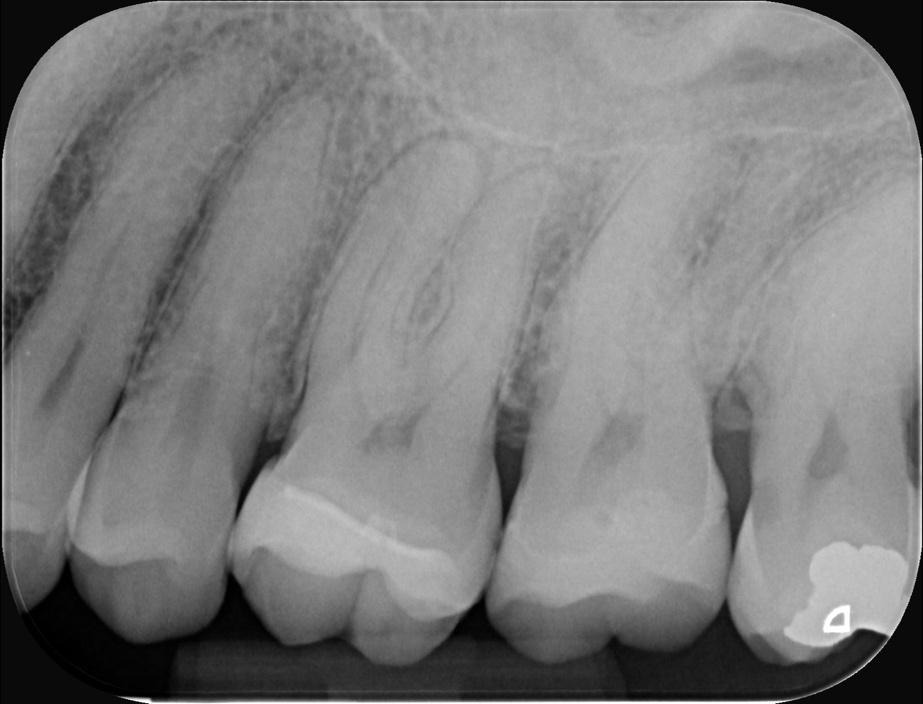

Conservative Access and Root Canal Preparation on a Curvy Molar with 4 Portals of Entry and 5 Portals of Exit

Diagnosis

Pulp necrosis and symptomatic apical periodontitis

Hybrid sequence of MiniKut 1503, TS 1802, TS 2004 in mb1, mb2 and db. The palatal was finished with a VDW Rotate 3004. This sequence was chosen to suit the narrow-calcified canals. It enabled slow and gradual enlargement of the canals which reduce the chance of the file breakage especially in the distobuccal canal with the ‘s’ shaped curve.